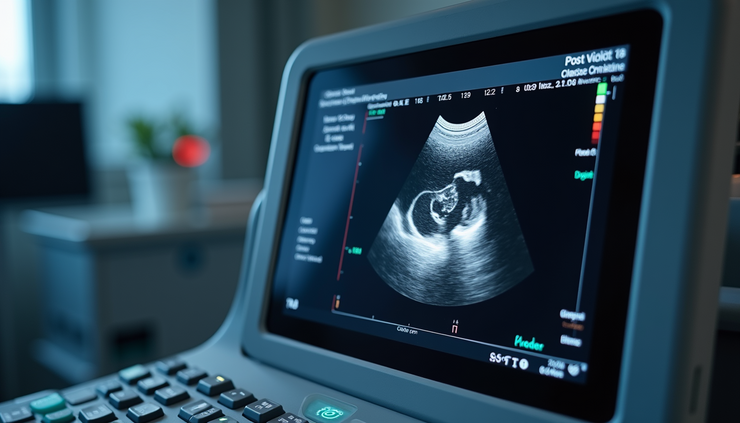

Bladder ultrasound used to measure post-void residual volume

Measuring PVR is a simple, non-invasive process often done using ultrasound. The bladder is scanned immediately after urination to estimate the amount of urine left inside. Other methods include:

Bladder scan devices: Portable ultrasound machines used in clinics or hospitals.